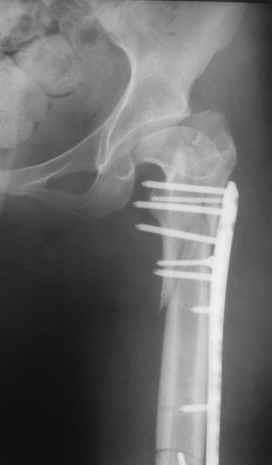

Уважаемые коллеги, приношу извенения за молчание. Готовили материал и боялись писать раньше времени. Все хотели убедиться в том, что после операции все будет спокойно. Спасибо за отклики и советы. К сожалению, гамма-гвоздя, штифтов с возможностью установки более 2-х блокирующих винтов у нас нет. Зато нашли достаточно длинную пластину с угловой стабильностью. После проведения предоперационной подготовки и планирования выполнили остеосинтез. В условиях рентгеноперационной, после репозиции дистрактором из одного разреза 5см в проксимальном отделе подкожно установили пластину. Пришлось выполнить дополнительный разрез до5см в проекции перелома диафиза в средней трети, из которого удалось репонировать перелом и выполнить фиксацию стягивающим винтом. Затем все завершилось наложением пластины с угловой стабильностью. Пластина оказалась достаточно длинной, что позволило перекрыть все переломы с фиксацией каждого отломка минимум 5-ю винтами. Синтез достаточно стабилен. Пациентка активизирована на 3-и сутки(снимки прилагаются). В настоящий момент пациентка выписана на амбулаторное лечение. Еще раз, огромное спасибо всем за помощь в выборе тактики и просто совете. С уважением Украинский Е.

Прошу прощения, со снимками глюк произошел. Высылаю. С уважением Евгений У.

Получилось очень симпатично, мои поздравления. А можно фото конечности без наклеек посмотреть?

И межфрагментарный винт на диафизе - так ли он нужен при выбранном варианте остеосинтеза с относительной стабильностью?

Хотя все-таки закрыто антгерадно заштифтовать тут было вполне можно, и при использовании отечетственного имплантата лечение обошлось бы на порядок дешевле. Опасения коллеги Кульджанова насчет кровоснабжения головки бедра и предстоящих операции в этой области кажуься несколько

преувеличенными - и стержень можно через вертел ввести, да и расстройства кровоснабжения головки, если они случатся после штифтования, не будут длиться вечно.

Но в люом случае, что сделано - то сделано, и сделанное выглядит вполне обнадеживающе, так что еще раз поздравляю коллег с успешным выходом из непростой ситуации.